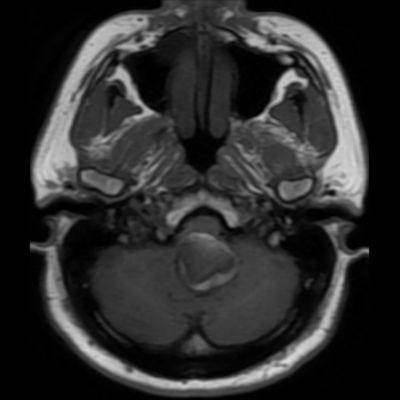

- A. Posterior fossada, T2A, T1A görüntü ve SWAN sekanslarda, 3.5 cm boyutta, düzgün sınırlı, T1A hiperintens, T2A hipointens heterojen iç yapıda kitlesel lezyon izleniyor (çember). Lezyonun serebellum ve kraniyoservikal bileşkeye bası etkisi mevcuttur (ok). Lezyon periferinde T1A, T2A ve SWAN görüntülerde hiperintens tubuler yapı bulunmaktadır (ok). Bu yapı intralezyonel “yılanvari eksantrik vasküler’’ yapıdır.

- Kısmen tromboze olmuş dev serebral anevrizma, kan ürünlerinin değişken yaşına bağlı olarak MRG’de heterojen bir sinyale sahiptir.

- T1 kısmen tromboze anevrizmada genellikle hiperintens odaklarla heterojen

- T2 kısmen tromboze anevrizmada genellikle hipointens odaklarla heterojen, serpantin anevrizma içi damar kanalında akım boşlukları, bitişik parankimde vazojenik ödem görülebilir.

- T2 ve SWAN genellikle santral-çevresel duyarlılık artefaktları görülür.